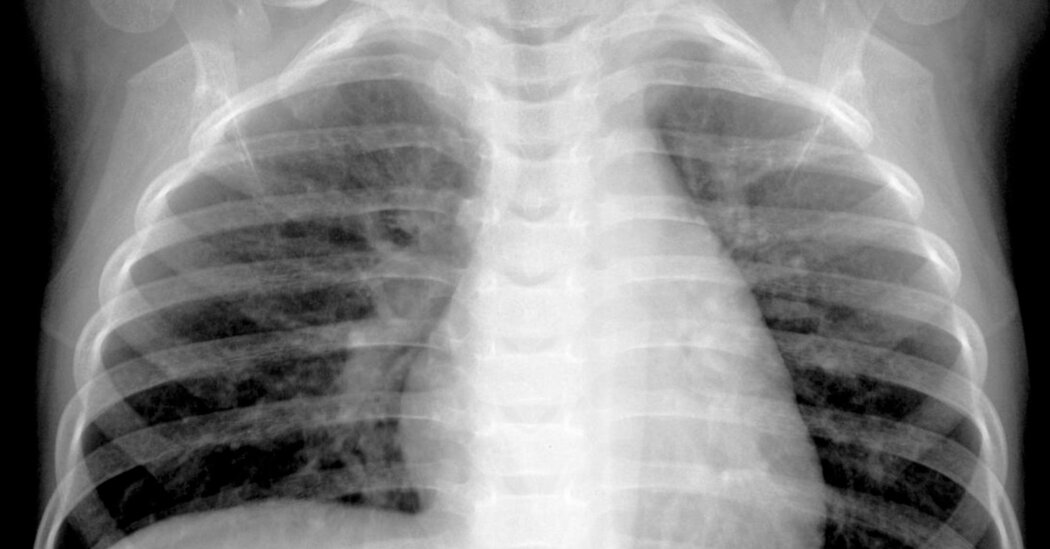

Most HMPV infections are mild, resembling bouts of the common cold. But severe cases can result in bronchitis or pneumonia, particularly among infants, older adults and immunocompromised people. Patients with pre-existing lung conditions, such as asthma, chronic obstructive pulmonary disease or emphysema, are at higher risk of severe outcomes.